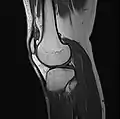

MRI

Both anterior cruciate ligament (ACL) and posterior cruciate ligaments (PCL) are hypointense on both T1 and T2 weighted images of MRI. However, some high signal striations are often seen at the distal part of the ACL, making ACL higher intensity than PCL on MRI scans.[17]

Knee MRI (PD TSE FS sagittal)